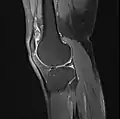

Imaging

MRI

Both anterior cruciate ligament (ACL) and posterior cruciate ligaments (PCL) are hypointense on both T1 and T2 weighted images of MRI. However, some high signal striations are often seen at the distal part of the ACL, making ACL higher intensity than PCL on MRI scans.[17]